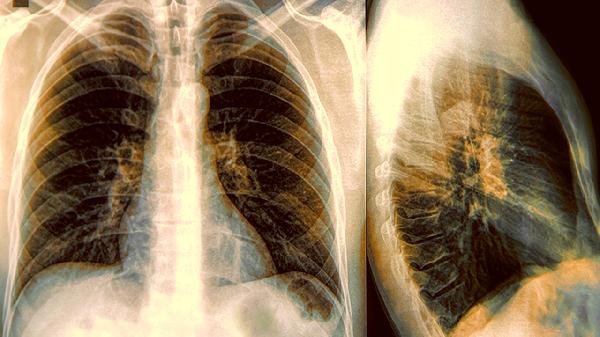

五、肺炎辅助治疗

在细菌性或病毒性肺炎的治疗中,羚羊清肺丸可作为辅助用药改善咳痰症状。肺炎患者多见高热、咳嗽、咯黄痰等表现,该药通过清热化痰功效配合抗生素治疗,但不可替代抗感染药物,须严格遵医嘱使用。